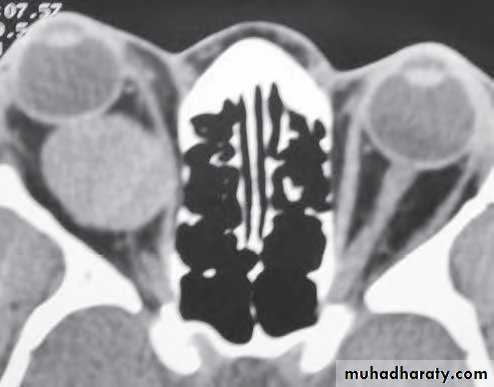

Investigation: CT shows a soft tissue mass with thinning or erosion of the bony walls of the sinus.

Treatment involves complete excision.